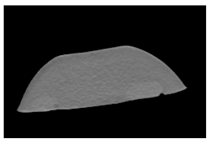

| CT-scan |  |  |  |

| CT-scan |  |  |  |

| CT-scan |  |  |  |

| CT-scan |  |  |  |

| CT-scan |  |  |  |

| CT-scan |  |  |  |